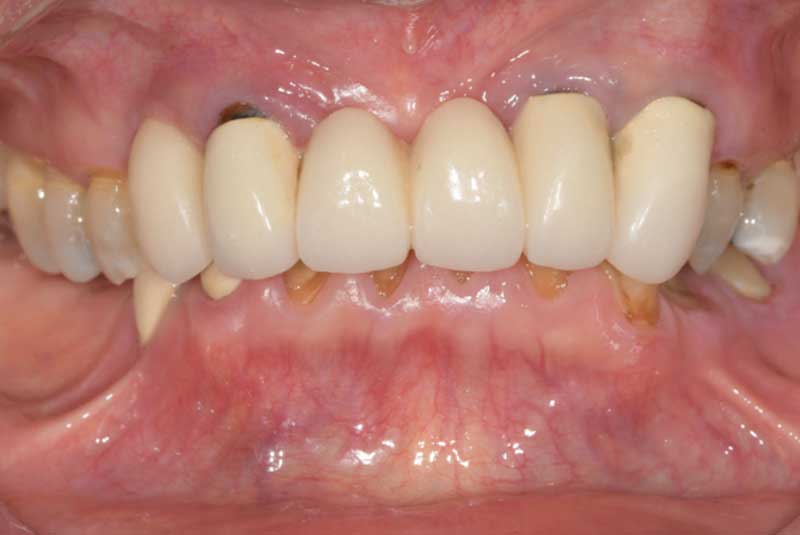

The patient had her implants placed 20 years ago. Four implants, particularly in the maxilla, were not positioned ideally for me to utilize and restore, while the four implants in the mandible were outdated and no longer functional. The patient's primary concern is to restore both function and aesthetics.

All on 6: Monolithic Zirconia Full arch prosthesis & Crown Lengthening, Veneers, Crowns, Onlays